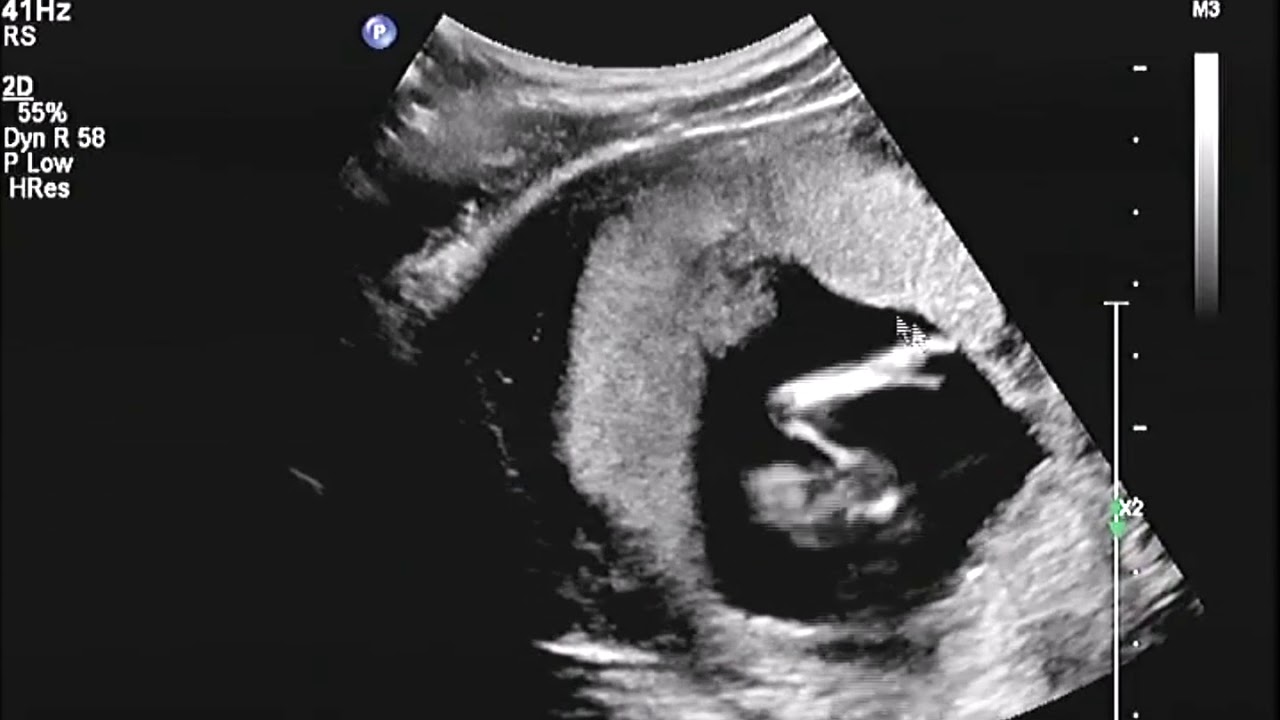

Rond de 10-13 weken krijg je een echo om te bepalen hoe lang je zwanger bent: de termijnecho.. Over de 13 wekenecho. Vanaf 12 weken en 3 dagen tot en met 14 weken en 3 dagen zwangerschap kun je een 13 wekenecho laten maken. De echoscopist kijkt met een echoapparaat naar de schedel, het hart, de buik, de armen en benen en de wervelkolom.. 13-weken echo. Vanaf 1 september 2021 is het mogelijk om de 13 weken echo te laten verrichten. De 13 wekenecho is, net als de 20 wekenecho, een onderzoek naar lichamelijke afwijkingen. De 13 wekenecho kan alleen plaatsvinden in de periode 12+3 tot en met 14+3 weken van je zwangerschap. Sommige (ernstige) afwijkingen zijn al te zien bij 13 weken.